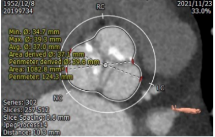

主动脉CT

瓣环平均直径:22.9mm

左室流出道平均直径:23.2mm

瓦士窦大小

横位心:50度

主动脉弓部角度平缓

入路条件尚可